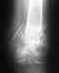

Здравствуйте.16.02.2013 упал с высоты 5 м. В результате закрытый перелом левой пяточной кости без смещения.

Наложили гипс и отправили домой.Когда можно будет вставать на ногу. и надо ли делать повторный снимок.